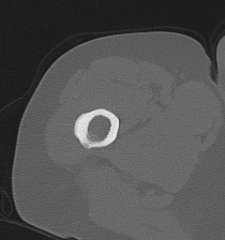

CT / MRI should be performed to exclude incomplete fracture

Atypical femur fracture xrayAtypical femur fracture CTAtypical femur fracture CT 2

Atypical FFAFF incomplete

Incomplete subtrochanteric AFF

Stress Fracture Lateral

Incomplete femoral shaft AFF / dreaded black line